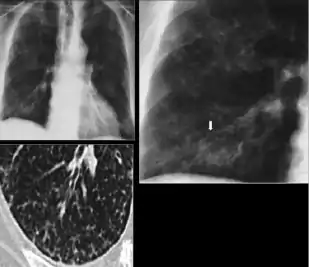

Chest x-ray showing nodule with margins that are indistinct or poorly defined (tree-in-bud sign) in post-primary pulmonary TB.

Chest x-ray showing nodule with margins that are indistinct or poorly defined (tree-in-bud sign) in post-primary pulmonary TB.